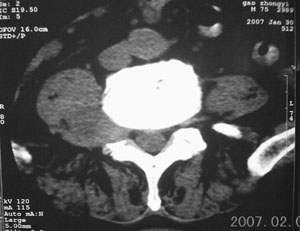

男,75岁,腰周疼5-6年。别无症状。

右侧椎旁、侧隐窝软组织肿块,呈不规则双极征改变,椎体后外缘骨质弧形压迹,椎间孔扩大;考虑神经源性肿瘤,神经鞘瘤可能性大,需与神经纤维瘤相鉴别。

病变侧椎间孔扩大,椎体缘受压吸收;

考虑神经源性肿瘤,神经鞘瘤可能;